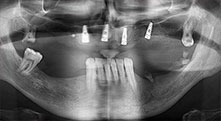

Could you give us a few surgical tips and tricks from your hospital?

Bratu: We like to use the sandwich technique for augmentation in the lateral mandible. A bone cover is prepared with the piezo saw and the crestal fragment is fixed with microscrews. We place a mixture of autologous bone and xenogenic bone replacement material in between. This works very reliably. You should always ensure sufficiently dimensioned vertical cuts when splitting the alveolar ridge in the mandible. Otherwise the bone may fracture easily.